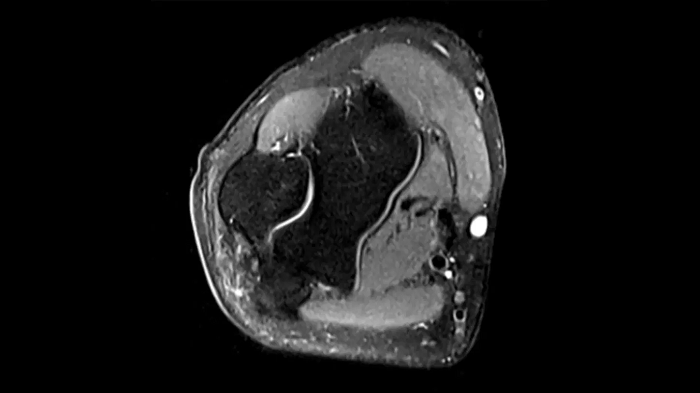

Knee

PD TSE Fat Sat with Deep Resolve and Simultaneous Multi-Slice

For clear imaging of the knee, outstanding fat suppression and performance are possible. Integrating the influence of Deep Resolve with the established Simultaneous Multi-Slice technique.

SMS 2 | Deep Resolve Gain & Sharp

0.4 x 0.4 x 3.0 mm2

TA 2:56 minutes

MAC-ID: 7aaaa0198.

MAC-ID: 7aaaa0198. Image Credit: Siemens Healthineers